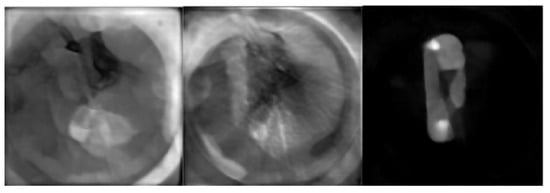

3.2. Results on miniPET-3 Data